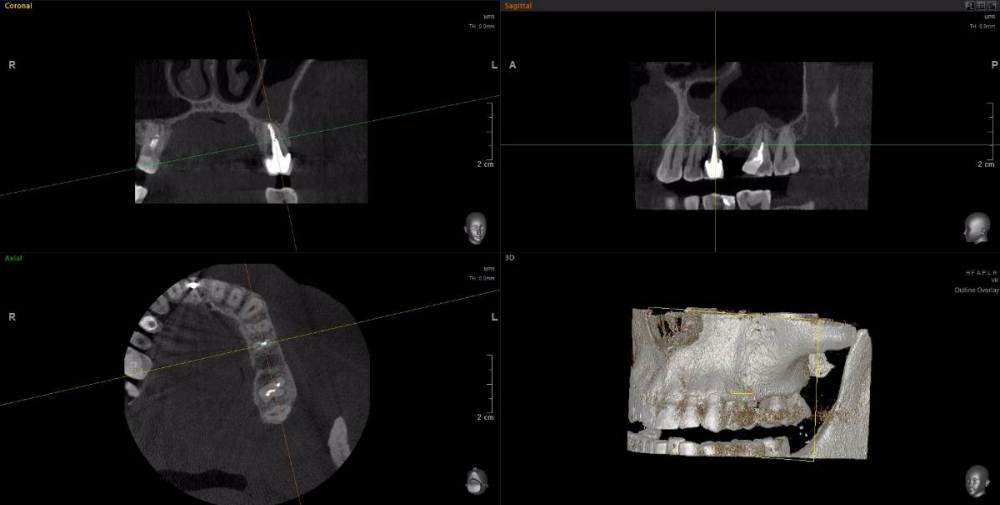

wladdX Опубликовано 15 апреля, 2021 Поделиться Опубликовано 15 апреля, 2021 Несколько скриншотов из вашей КЛКТ. Зуб 25: Зуб 27: Правая сторона: 1 Ссылка на комментарий

red_butler Опубликовано 16 апреля, 2021 Поделиться Опубликовано 16 апреля, 2021 1.5 1.6 перелечивать, 2.4 похоже кариес корня, нужно смотреть очно, 2.5 парадонтологическое поражение, смотреть очно, 2.6 ревизия корневых каналов Ссылка на комментарий